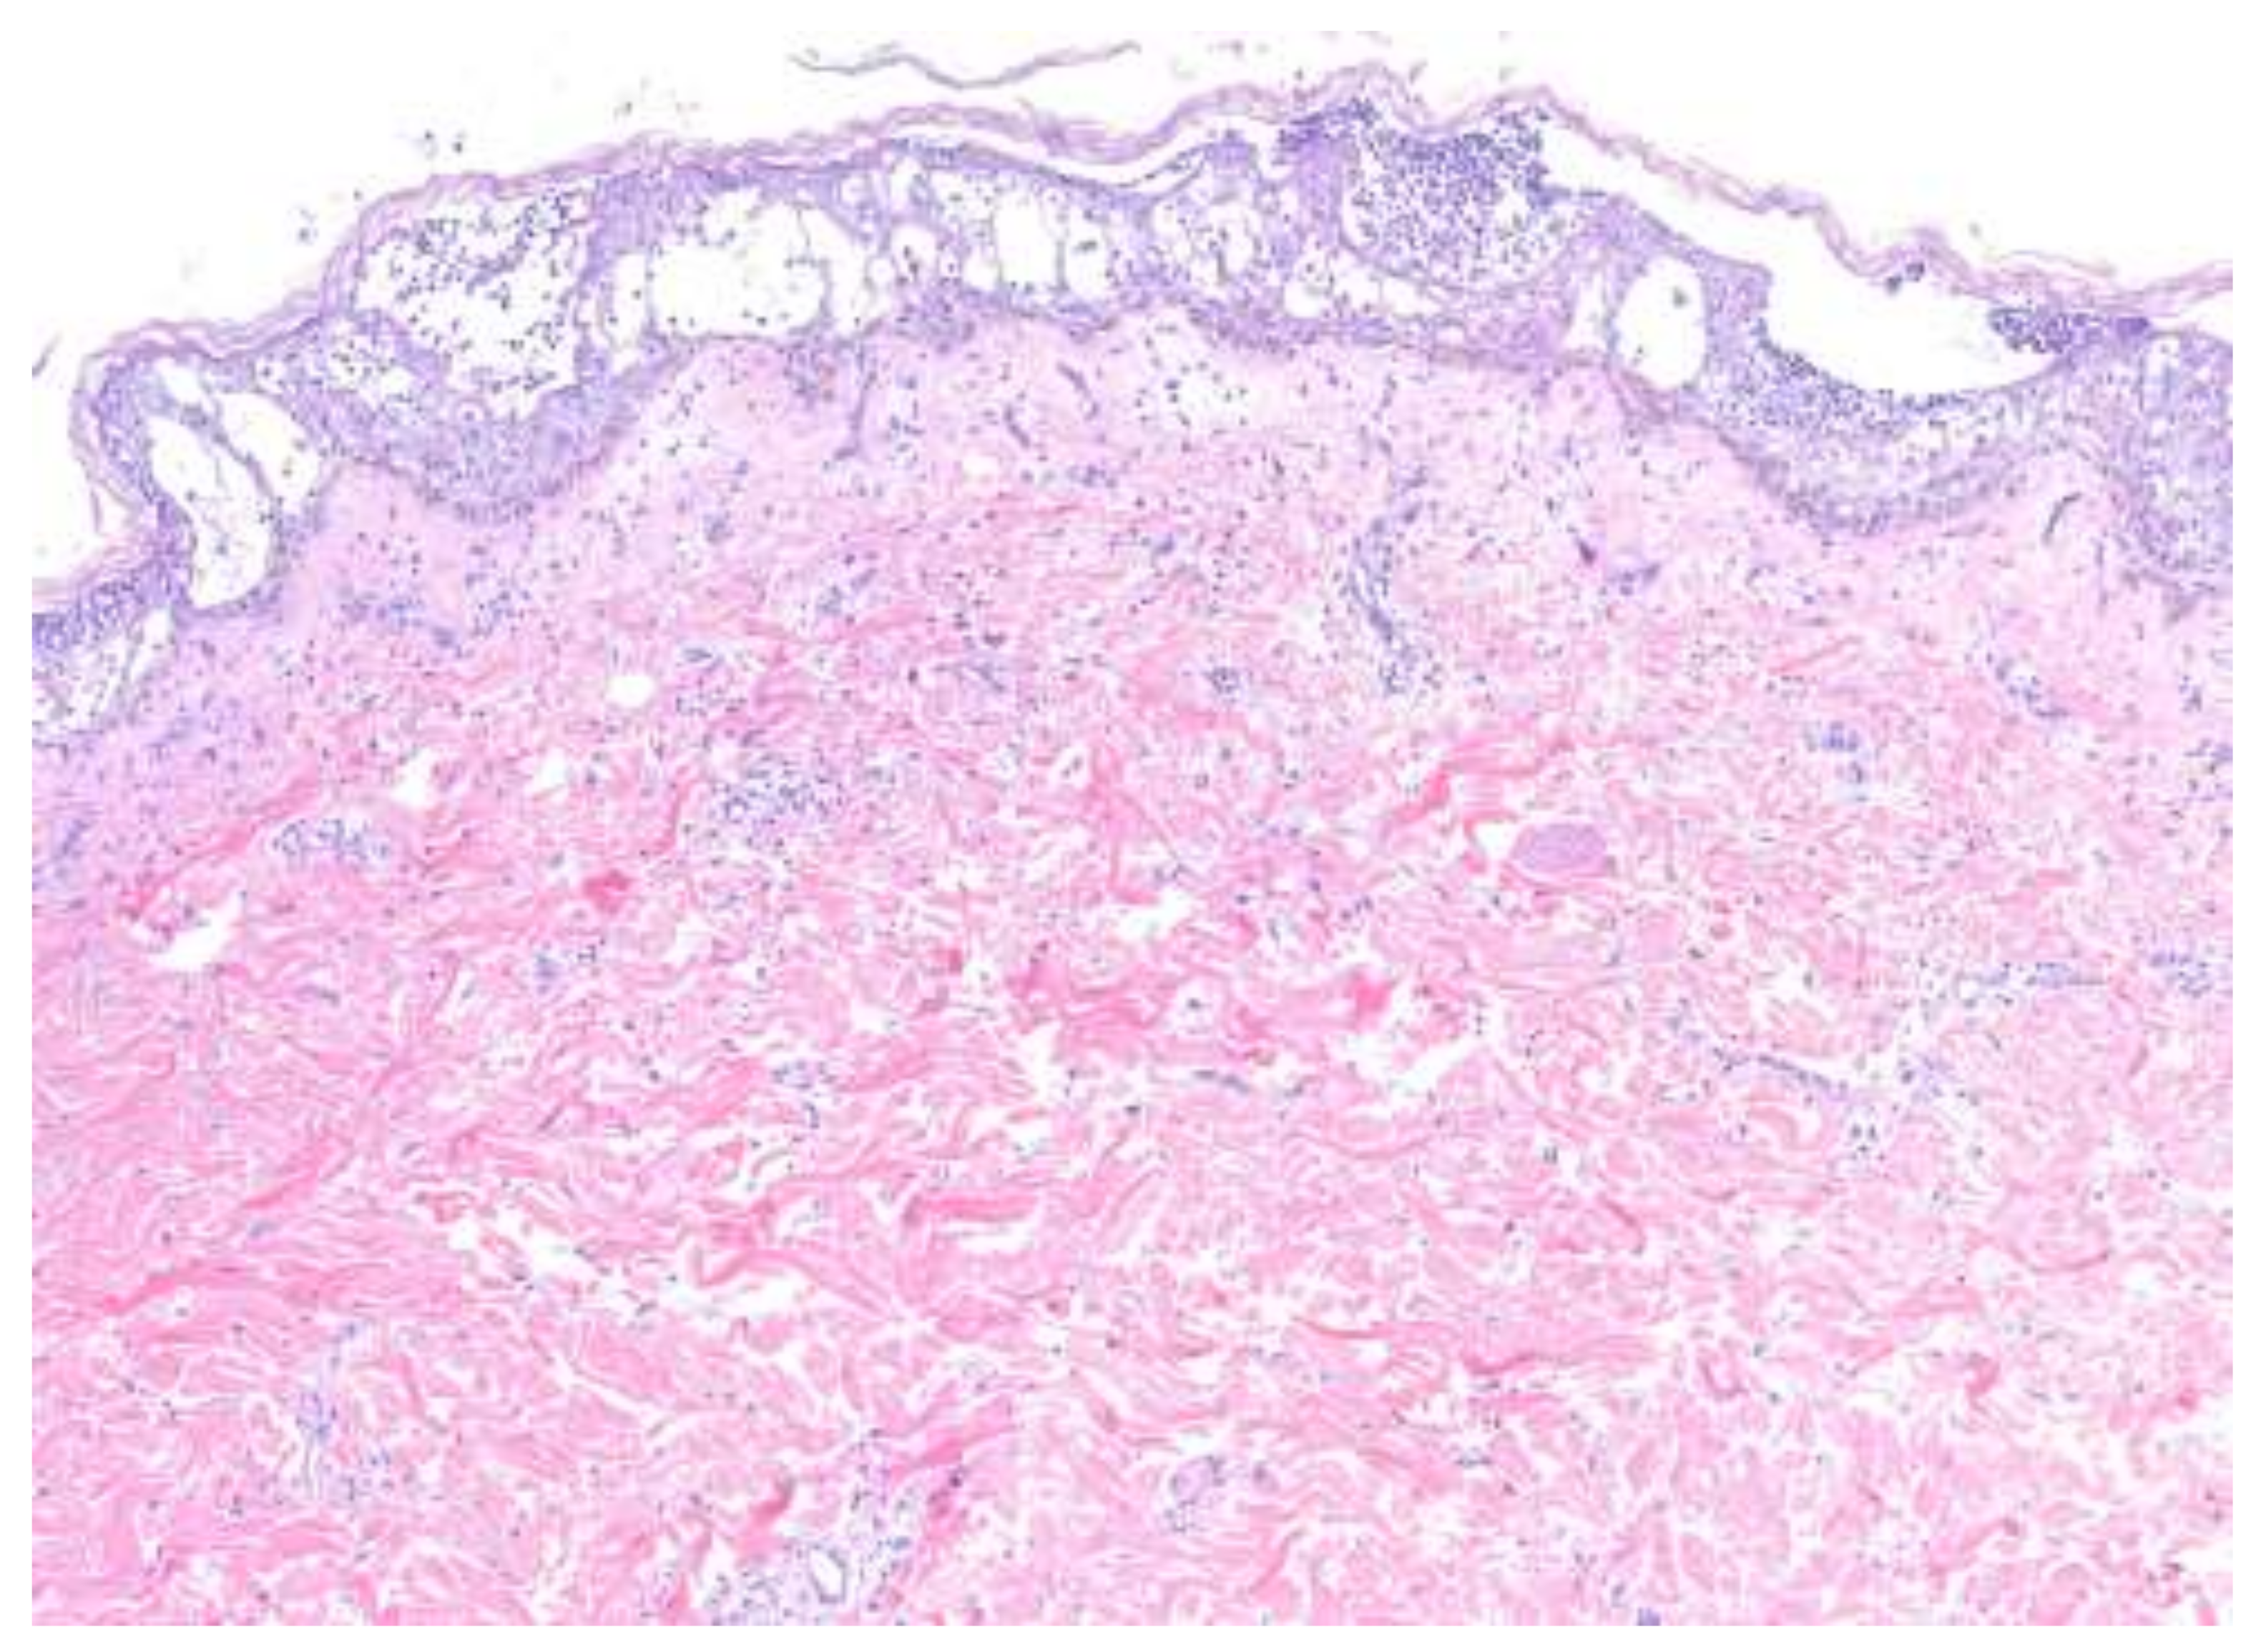

On histopathology, PP (Figure 3) is characterized by neutrophilic infiltrates with the presence of spongiform pustules of Kogoj in the stratum spinosum and microabscesses of Munro with the stratum corneum [3,4], both of which constitute the hallmark features of active psoriasis [8]. The accumulation of neutrophils is readily observed in the stratum corneum, surrounded by parakeratosis [8]. APP specifically presents with subcorneal pustules, while PPPP additionally demonstrates eosinophilic and mast cell infiltrates in the upper dermis [4]. PP shows the same characteristic epidermal changes of PV, with psoriasiform elongation of the rete ridges and broad parakeratosis. However, instead of the smaller micropustules seen in PV, larger macropustules are seen in the variants of PP [31].

The histopathologic features of PP and AGEP share many similarities and, at times, may be indistinguishable. Biopsies of AGEP (Figure 4) characteristically show subcorneal and intraepidermal spongiform pustules according to EuroSCAR histopathologic criteria. In a study of 102 cases of AGEP, subcorneal pustules, intraepidermal pustules, or a combination of the two were seen in 41%, 20%, and 38% of cases, respectively [22]. Psoriasiform hyperplasia with rete ridge elongation and clubbing was seen in 76% and 51% of cases, respectively. Papillary dermal edema and a mixed inflammatory infiltrate are seen in the vast majority of cases.

Figure 3. Generalized pustular psoriasis. Subcorneal pustular dermatitis with irregular epidermal hyperplasia and sparse dermal infiltrate.

Figure 4. Acute generalized exanthematous pustulosis. Spongiform pustules and papillary dermal edema are consistent features. Orthokeratosis reflects the acuity of this process.